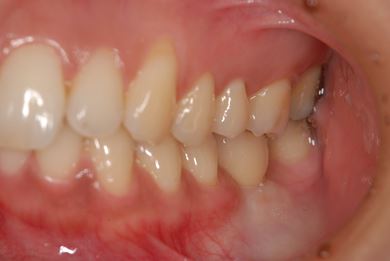

| 性別/年齢 | 女性 / 30歳 | ||||||||||||||||||||||||||||||||

| 主訴 | 銀歯がはずれた奥歯にひびが入っており、抜歯しなければいけないため、インプラントの治療相談を希望。 | ||||||||||||||||||||||||||||||||

| 治療内容 | インプラント1本、メタルボンドセラミック1本 | ||||||||||||||||||||||||||||||||